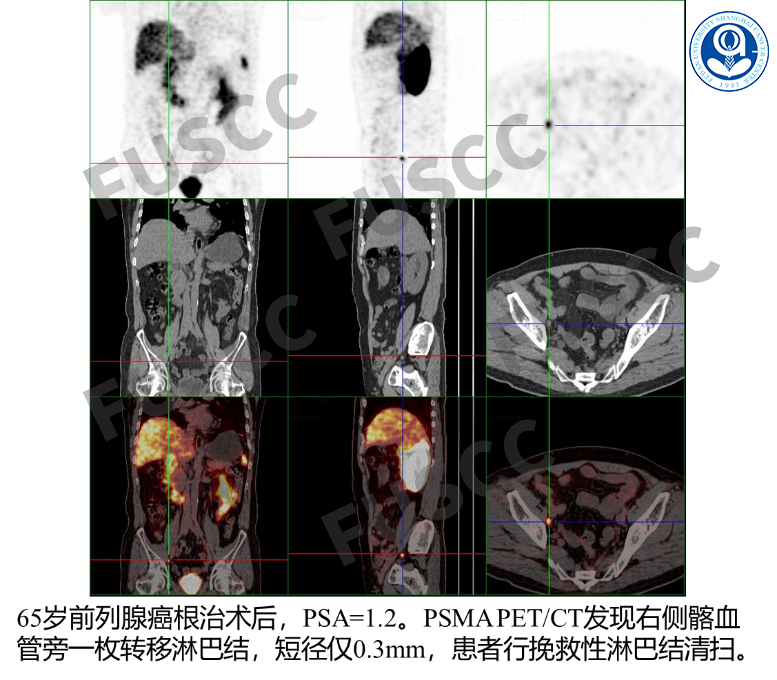

03

生化复发监测

前列腺根治术后PSA大于0.2ng/ml,或前列腺癌根治性放疗后PSA大于2.0ng/ml,推荐PSMA检查以指导临床治疗决策的制定。